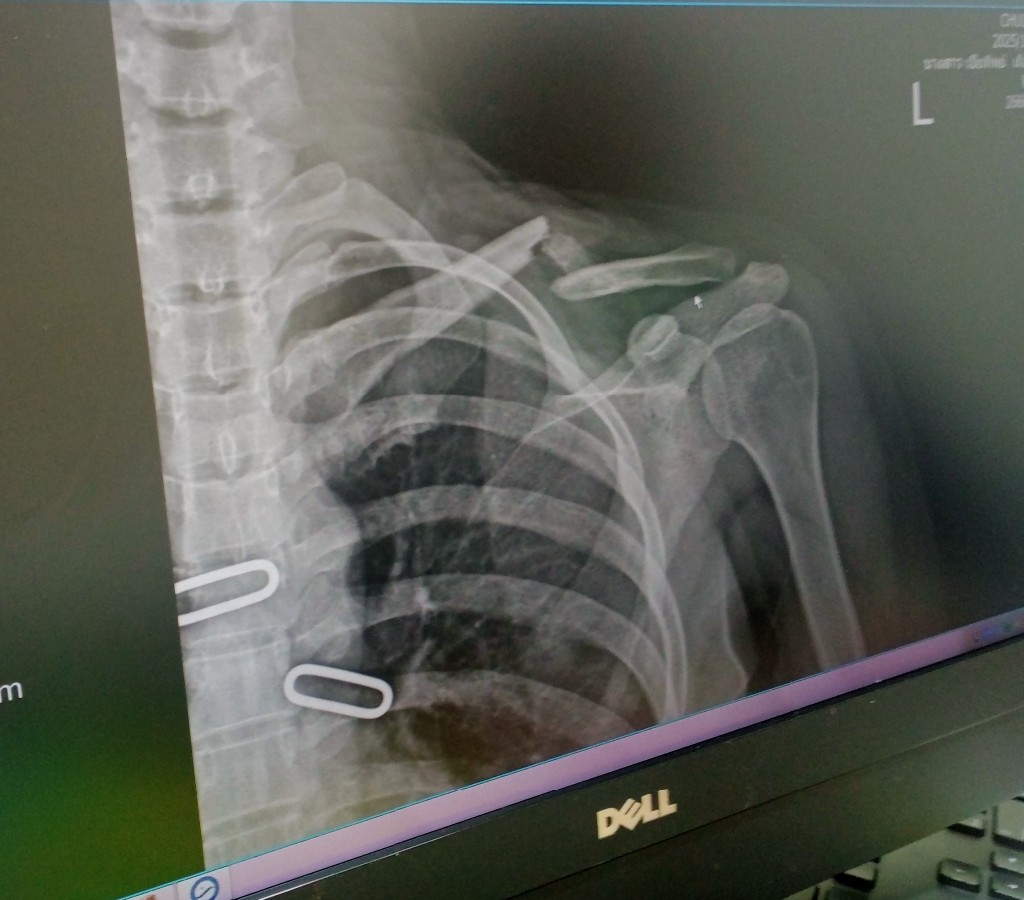

๑. กระดูกไหลาร้าหัก .. ส่วนใหญ่ ไม่ต้องผ่า แต่ หายแล้วกระดูกจะติดผิดรูป (กระดูกนูน) อาจไม่สวยงามแต่มักไม่มีปัญหาในการใช้งาน

๒. การผ่าตัด ก็มีความเสี่ยง มีข้อเสีย ถ้าไม่จำเป็น ก็ไม่ควรผ่า

ปล. ถ้าเป็นผม ดูเฉพาะภาพเอกซเรย์ ผมก็เลือก วิธี ไม่ผ่าตัด แล้วติดตามดูอาการเป็นระยะ

กระดูกไหปลาร้าหักแบบนี้ควรผ่าดีไหม? แต่บอกที่รักษาบอกไม่ต้องผ่า

ควรไปรักษากับหมอท่านอื่นดีไหมค่ะ

ภาพเอ๊กซ์เรย์ ครั้งที่ 2 ค่ะ